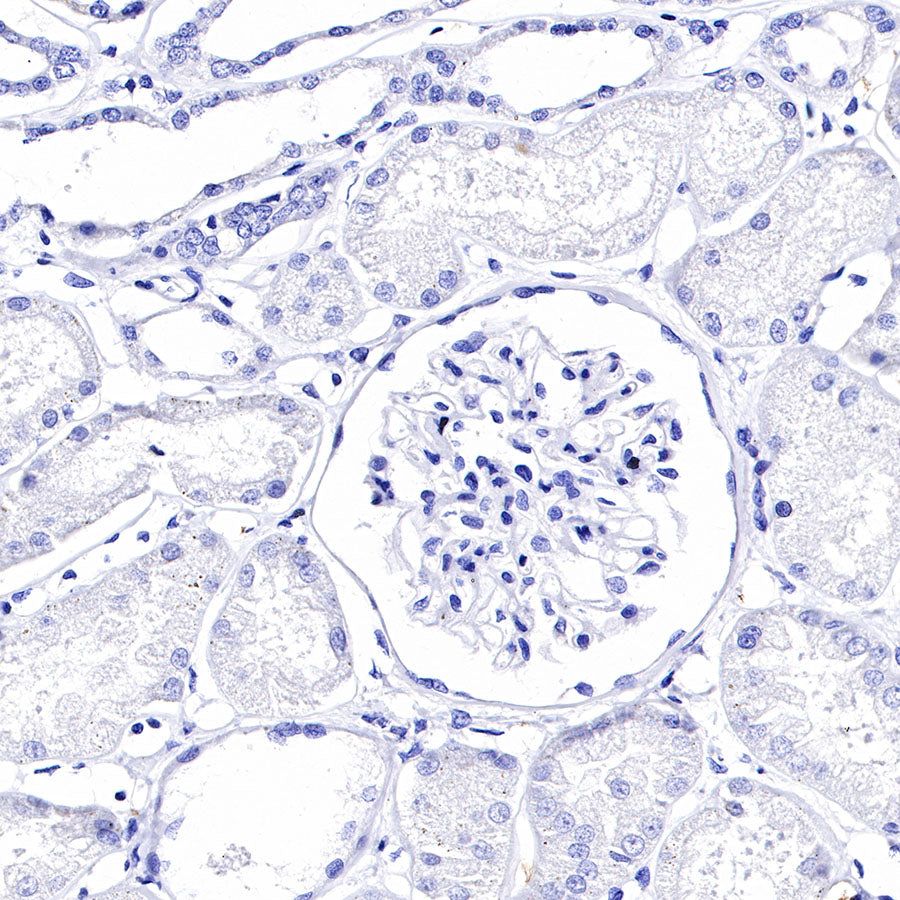

Negative control: IHC shows negative staining in paraffin-embedded human kidney. Anti-GPA33 antibody was used at 1/2000 dilution, followed by a HRP Polymer for Mouse & Rabbit IgG (ready to use). Counterstained with hematoxylin. Heat mediated antigen retrieval with Tris/EDTA buffer pH9.0 was performed before commencing with IHC staining protocol.